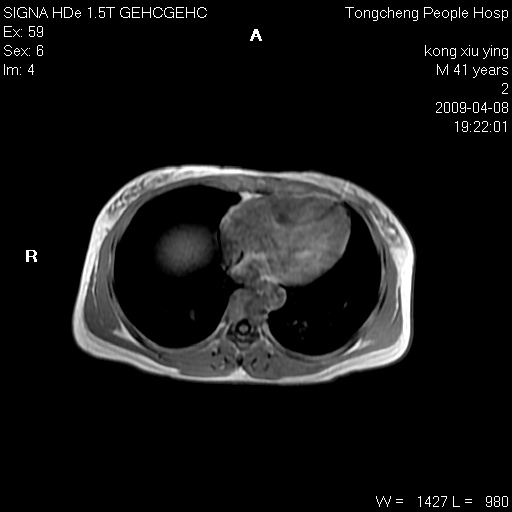

标题: CL1008:【经典】胆囊石榴籽样结石。 [打印本页]

标题: CL1008:【经典】胆囊石榴籽样结石。

女,41岁。健康体检——彩超提示:胆囊显示不清。平素健康,无不适感。

腹部mr扫描及mrcp,图像如下:

胆囊石榴籽样结石。